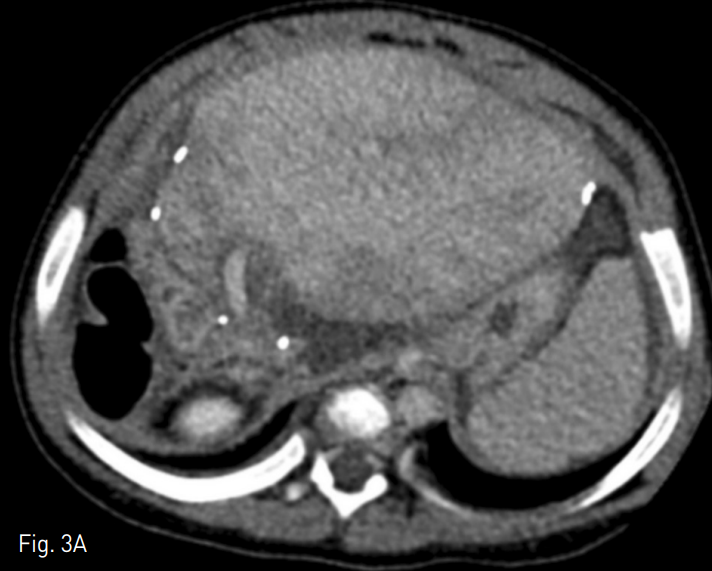

Fig. 3

A. Contrast-enhanced computed tomography revealed geographic hepatic parenchymal enhancement which reflects hepatic conges tion.

B. There was no filling defect or thrombosis in the hepatic vein and the stent (arrow).

시술 후 환자의 컨디션과 혈액 검사 소견 호전되어 퇴원하였으나 시술 2주 후 다시 복부 팽만과 식이 섭취감소를 호소하며 내원하였다. 혈액 검사 소견 상 혈소판 수치 혈소판 수치 106,000/mm3, INR 1.82, albumin 3.4g/dL, total bilirubin 1.1mg/dL, AST 48U/L, ALT 49U/L로 첫 시술 전 보다는 정도가 낮으나 악화되어 있었다. 전산화 단층 촬영 상 간실질의 울혈을 시사하는 간실질의 불균질한 조영 증강이 관찰되었으며, 스텐트 내 충만결손 병변은 관찰되지 않았다(Fig. 3). 다시 환자의 내경정맥을 통해 5 Fr 혈관조영술용 카테터를 삽입하여 간정맥 내로 진입하였으며, 조영제 주입 시 혈류 정체와 함께 스텐트의 끝 주변으로 협착이 관찰되었으며 압력 차이는 19mmHg로 측정되었다 (Fig. 4A). 간정맥 협착 해소를 위해 14mm x 30mm 자가확장형 스텐트 (Zilver)를 삽입하고 8mm x 40mm 풍선 카테터 (Mustang)을 이용하여 혈관성형술을 시행하였다. 이후 시행한 간정맥 조영술 상 우심방으로의 혈류가 회복되었으며 압력 차이가 3mmHg로 줄어들었다 (Fig. 4B).